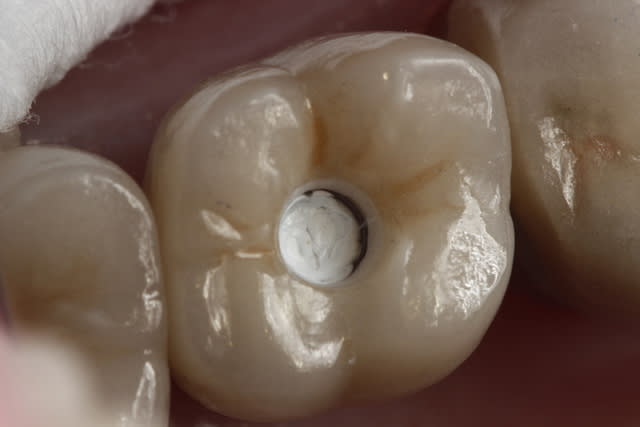

En ce qui concerne le choix entre ccc et ccm, il faut savoir que 90 % de mes couronnes sont en emax, mais dans le cas de racines extrêmement colorées ( ce qui est le cas ici)mon choix se porte sur des ccm classiques pour masquer ces colorations radiculaires que même une chape opaque sur emax ne peux dissimuler aussi bien qu'une ccm.

Bien sur la chape opaque emax est opaque est permet des réalisations très esthétique, je suis d'accord avec toi.

Mais ici il s'agit de dents ant sur racines naturelles, et toi tu montres une emax trans-vissé sur implant sur une dent post.

Cela n'a rien a voir. On ne peut pas comparer ce qui n'est pas comparable.

- la limite sur une couronne implantaire est souvent plus enfoui par choix ou par obligation qu'une couronne

- le biotype est souvent plus épais en post qu'en ant.

- la finition de la chape métal vest peut être plus proche de la ligne de finition vest du fait de sa finesse/chape pressé emax.

- tu cimentes tes ccm: ciment blanc opaque.

- tu colles tes emax. composite non opaque.

Pour avoir fait l’expérience plusieurs fois je préfère dans ce cas précis et pour ces raisons des ccm que des emax.

l’esthétique sera beaucoup facile a gérer surtout avec un cas plurale et symétrique.